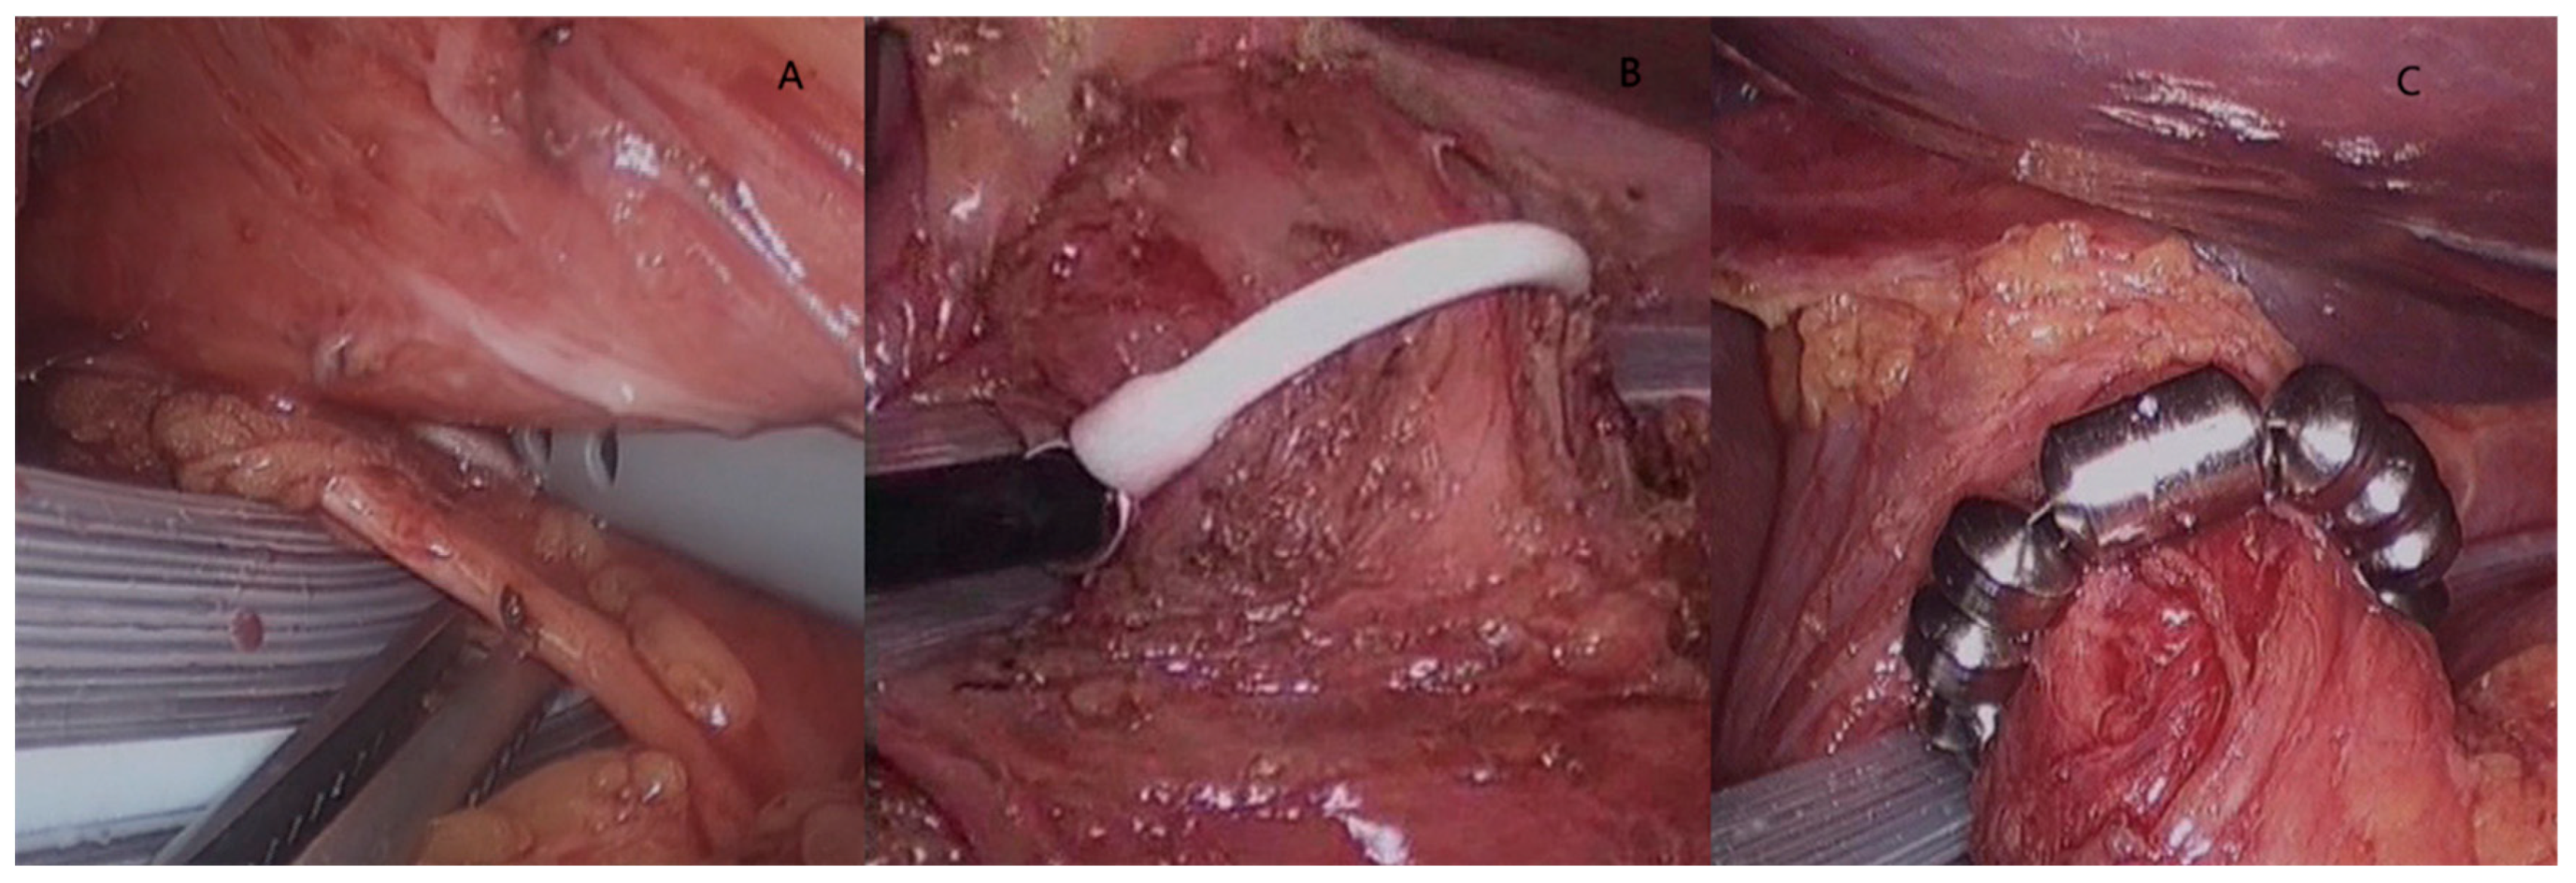

The Magnetic Sphincter Augmentation procedure (LINX TM) was originally designed as a gastric-sparing operation not requiring division of the short gastric vessels and indicated in young patients with progressive GERD. The procedure is performed laparoscopically and consists of implanting a ring of magnets around the esophagogastric junction (Figure 3). In the absence of hiatal hernia, only a limited dissection with preservation of the phrenoesophageal ligament is necessary [50].

Figure 3.

The LINXR procedure. After excluding the posterior vagus nerve (A) and sizing the distal esophagus (B), the magnetic sphincter augmentation device is placed at the esophago-gastric junction (C). The magnetic force between the beads decreases upon swallowing to accommodate the bolus; in the resting position, the magnetic bonds of the device augment the resistance of the lower esophageal sphincter to prevent reflux.